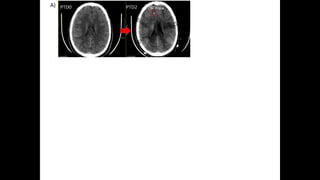

• #17 21 y/o s/p high-speed MCC Initial post-resus GCS 6T Initial CT with likely DAI Initially admitted to SICU An MRI was performed confirming diffuse axonal injuries. He was still in the SICU; someone began talking with the parents about potentially withdrawing care.

• #18 MMM Placed 51 hours from injury, PTD2.

• #19 MMM Placed 51 hours from injury, PTD2.